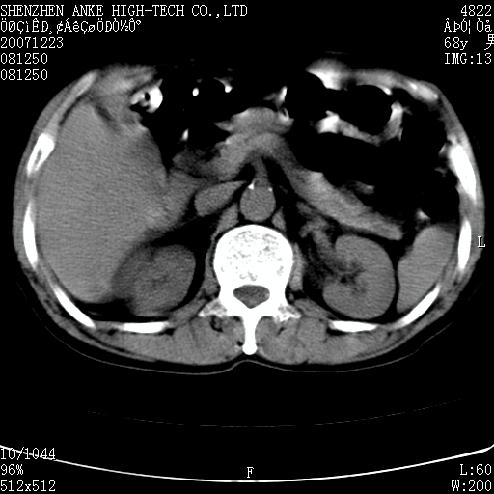

患者:男,63岁,2年前胆囊切除术后,现右上腹部剧烈疼痛近2天.

有无外伤史?右肾包膜下血肿可疑。

主要是问右肾有没有问题?患者无明显外伤史.

未见异常,病人差闭气,伪影较多.

肠管积气明显.

肠道准备不好,干扰影大。

肠道气体伪影干扰太大了,应该是干扰所致,未见明显异常。

肠道准备不好,胃底后壁显示不清,右肾改变考虑为伪影。

上腹部ct平扫未见明显异常。(肠道气体较多,患者呼吸了)